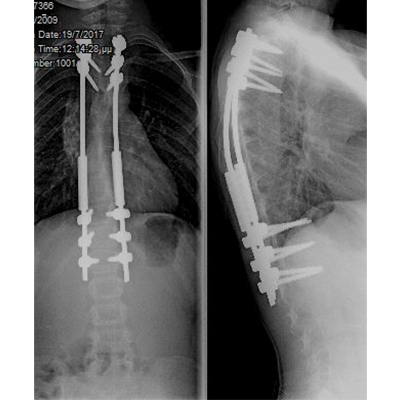

Σύνθετες παραμορφώσεις της σπονδυλικής στήλης όπως είναι η σκολίωση και η κύφωση, ακόμα και σε περιπτώσεις παιδιών με συγγενείς ανωμαλίες ή νευρομυϊκές παθήσεις, αντιμετωπίζονται χειρουργικά και στις μικρότερες ηλικίες. Τα σύγχρονα συστήματα σπονδυλοδεσίας επιτρέπουν τη διόρθωση της παραμόρφωσης, με παράλληλη επιμήκυνση της σπονδυλικής στήλης, ενώ το παιδί συνεχίζει να αναπτύσσεται και να ψηλώνει. Αποτέλεσμα είναι τα παιδιά - αλλά και οι οικογένειές τους - να ξεπερνούν με ασφάλεια και να αφήνουν οριστικά πίσω τους ένα δύσκολο πρόβλημα, όπως είναι μια παραμόρφωση της σπονδυλικής στήλης, συνεχίζοντας πια να αναπτύσσονται φυσιολογικά συμμετέχοντας σε όλες τις δραστηριότητες των παιδιών της ηλικίας τους.

Διατεινόμενη σπονδυλοδεσία σε παιδική νευρομυϊκή σκολίωση. Το παιδί συνεχίζει να ψηλώνει, καθώς η σπονδυλική του στήλη επιμηκύνεται.